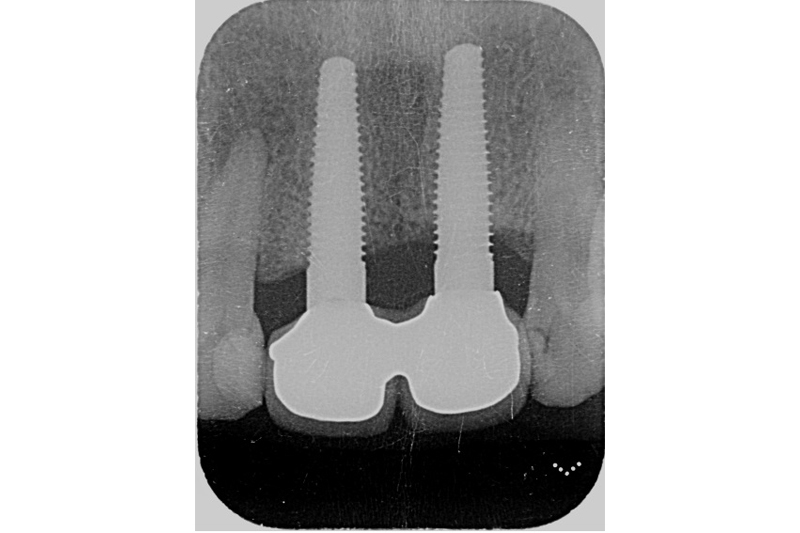

根尖X光片術前

根尖x光片術後

植體植入,置放於理想的水平與垂至高度位置